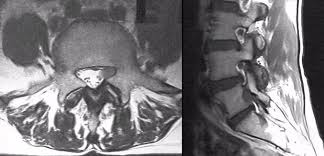

Nerve root pain is variably described as knifelike or aching and is widely distributed projecting to the sclerotome defined as deep structures such as muscles and bones innervated by the root. Lumbar Radiculopathy Nerve Root Compression Lumbar radiculopathy refers to disease involving the lumbar spinal nerve root. The Laser Spine Institute lists sciatica symptoms as pain numbness tingling and burning.

Lumbar radiculopathy is typically caused by a compression of the spinal nerve root. Typically root pain is aggravated by coughing sneezing and straining at stool actions that require a Valsalva maneuver and raise intraspinal pressure. Loss of strength reflex and sensation occurs in the territory of the compressed root. There is a significant volume of literature that would point to the neural tissues themselves as the most logical structures for future research that attempts to interfere with the natural history of this disease from the standpoint of pain. It is defined as sudden usually unilateral severebrief stabbing lancinating recurring pain in the distribution of one or more branches of the Vth cranial nerve Trigeminal neuralgia also known as prosopalgia or fothergills disease is aneuropathic disorder characterized by episodes of intense pain in the face originating from trigeminal nerve. Herniated disc causing a single nerve root compression leg pain back pain. An estimated 20 million Americans suffer from peripheral nerve damage aka.